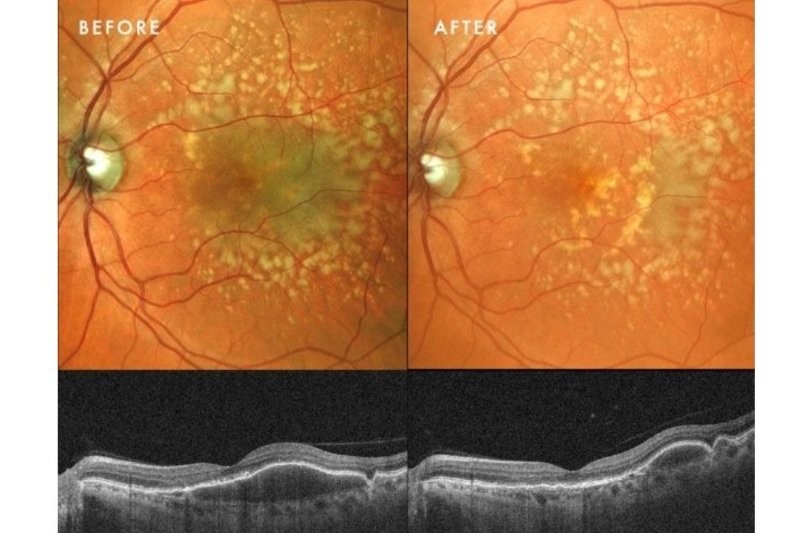

Case 2: Prior drusenoid PED resolution with RPE atrophy

This case serves as a counterpoint to Case 1, illustrating the typical natural history of drusenoid PED collapse: progression to atrophy. It also shows the value of patient education through organistions such as Macular Degeneration New Zealand (MDNZ).

Clinical presentation: A 71-year-old man presented with a history of drusenoid PEDs first noted in 2022. Following discharge from public hospital services (reflecting the standard ‘watch and wait’ approach), he sought a referral for PBM after reviewing literature provided by MDNZ. Examination revealed that, since 2022, his PEDs had spontaneously resolved but, unlike Case 1, had progressed to moderate GA involving the foveal centre in both eyes.

Case 2, Fig 2. This demonstrates the typical natural history of drusenoid PED resolution. There was a relatively rapid change from no atrophy initially, to moderate geographic atrophy over a 3-year period

Response to therapy: Despite the presence of established atrophy, he demonstrated a robust functional response. BCVA in the better eye improved significantly from 6/15 to 6/9, while the more severely affected fellow eye improved from 6/30 to 6/24.

Clinical implication: This aligns with the concept that PBM targets the ‘penumbra’ – the ring of stressed but viable cells surrounding atrophic areas. It demonstrates that structural loss does not preclude functional gain. By optimising the bioenergetics of the remaining photoreceptors, it is possible to stimulate visual recovery, even in eyes with foveal involvement.